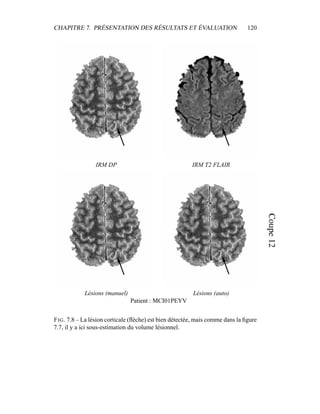

c’est donc sur elle que portera l’analyse lors de la segmentation en tissus et de la

présentation du modèle de volume partiel. Les autres modalités seront utilisées a

posteriori.

4.4 Segmentation en tissus.

4.4.1 Algorithme

Le but de cette segmentation en tissus sains est leur caractérisation, afin de

pouvoir construire un premier processus de détection des lésions de SEP. Même

si les 4 séquences (T2 FSE / DP, T1, T2 FLAIR) sont disponibles, la segmenta-

tion ne sera menée dans un premier temps que sur le couple T2/DP, alors que les

autres séquences – T1, T2 FLAIR – montreront tout leur intérêt pour la détection